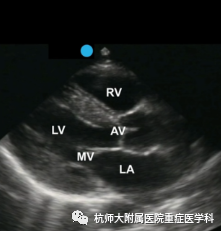

a.胸骨旁长轴切面:位置选择:胸骨左缘第2-5肋间,超声探头标记点指向右肩。操作过程中探测平面基本与右肩至左季肋部连线相平,超声探头束指向患者后背方向。滑动超声探头找到胸骨旁长轴平面,通过转、摇、倾三个动作小幅度调整超声探头以获取最佳标准图像。

主要评估内容:(1)心脏房室大小与大体形态比例改变;(2)左心室流出道异常变化(如有无梗阻等);(3)室间隔、左心室后壁运动,室壁厚度的变化;(4)主动脉瓣、二尖瓣瓣膜形态改变与异常血流;(5)有无心包积液;